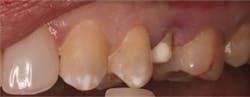

Figures 2 and 3: Additional restorations using Lava Esthetic